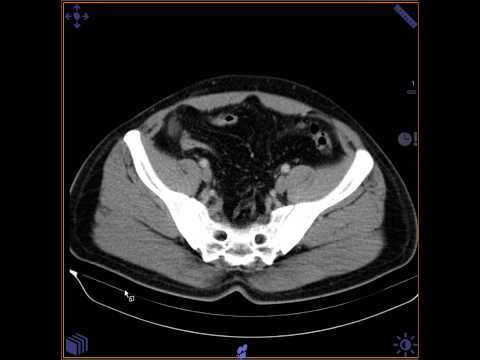

Scenography shows “sentinel loop” sign in the left lower quadrant. Enhanced axial CT demonstrates an ovoid inflamed fatty mass (arrow).

Omental infarction has a clinical presentation similar to that of epiploic appendagitis, with the infarcted fatty tissue being a segment of the omentum. CT demonstrates an ovoid inflamed fatty mass, larger than in epiploic appendagitis and lacking a hyperdense ring on CT [1].